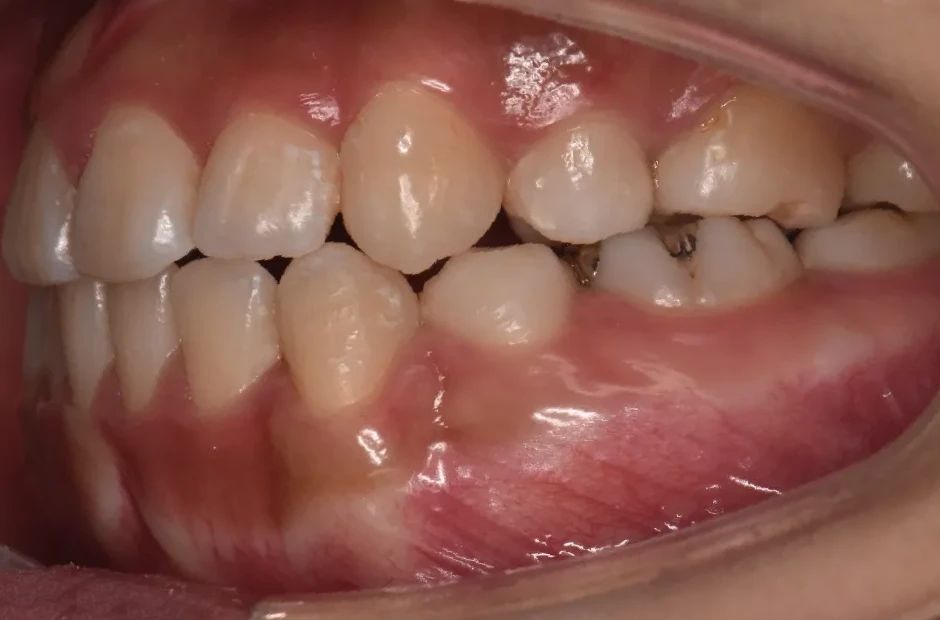

治療症例

ブラケット矯正

前歯部反対咬合

| 診断名・主訴 | 前歯部反対咬合 |

|---|---|

| 年齢・性別 | 14歳・男性 |

| 治療期間・回数 | 1年2か月 |

| 治療に用いた主な装置 | ブラケット矯正 |

| 抜歯部位 | なし |

| 治療費 | 60万円(税抜) |

| リスク・副作用 | 装置による違和感・疼痛・歯肉退縮・歯根吸収・虫歯のリスクなど |

治療前

治療中

治療後